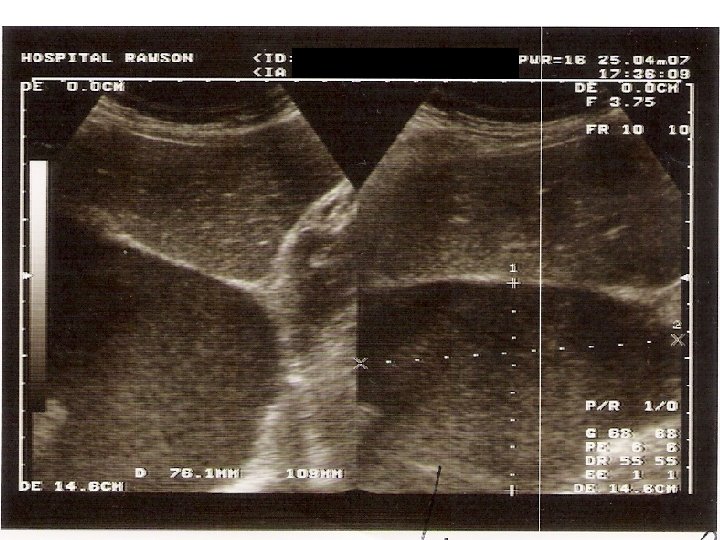

Aproximación diagnóstica: Ecografía n n Indicaciones Confirmación de DP en casos no claros Guiar punción en derrames pequeños o tabicados Ha demostrado reducción en la incidencia de Neumotórax (Evidencia C) Porcel JM, Light RW. Diagnostic aproach to pleural effusion in adults. Am Fam Physician 2006: 73: 1211